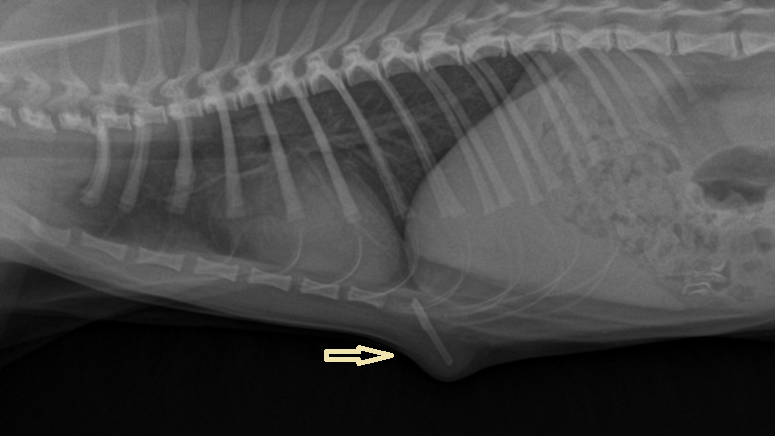

고양이와 반려견의 새가슴 혹은 볼록가슴과 심장병

즉, 새가슴(pectus carinatum)이 있는 경우 사람과는 달리 선천성 심장질환과 연관되어 있다는 언급. HCM이나 DCM을 말하는 것.

심장도 발생학적으로 중배엽 유래이고 뼈도 중배엽이라 뼈의 기형이 유발되는 발생상의 문제라면 동일한 중배엽의 발생에도 영향이 있을 수밖에 없지 않은가? 라는것. 특히 pectus carinatum은 뼈의 배열 문제이고, HCM나 DCM 같은 심장 질환도 심근 세포의 배열 문제니까. 물론 이는 이해를 쉽게 하기 위한 추정이다.